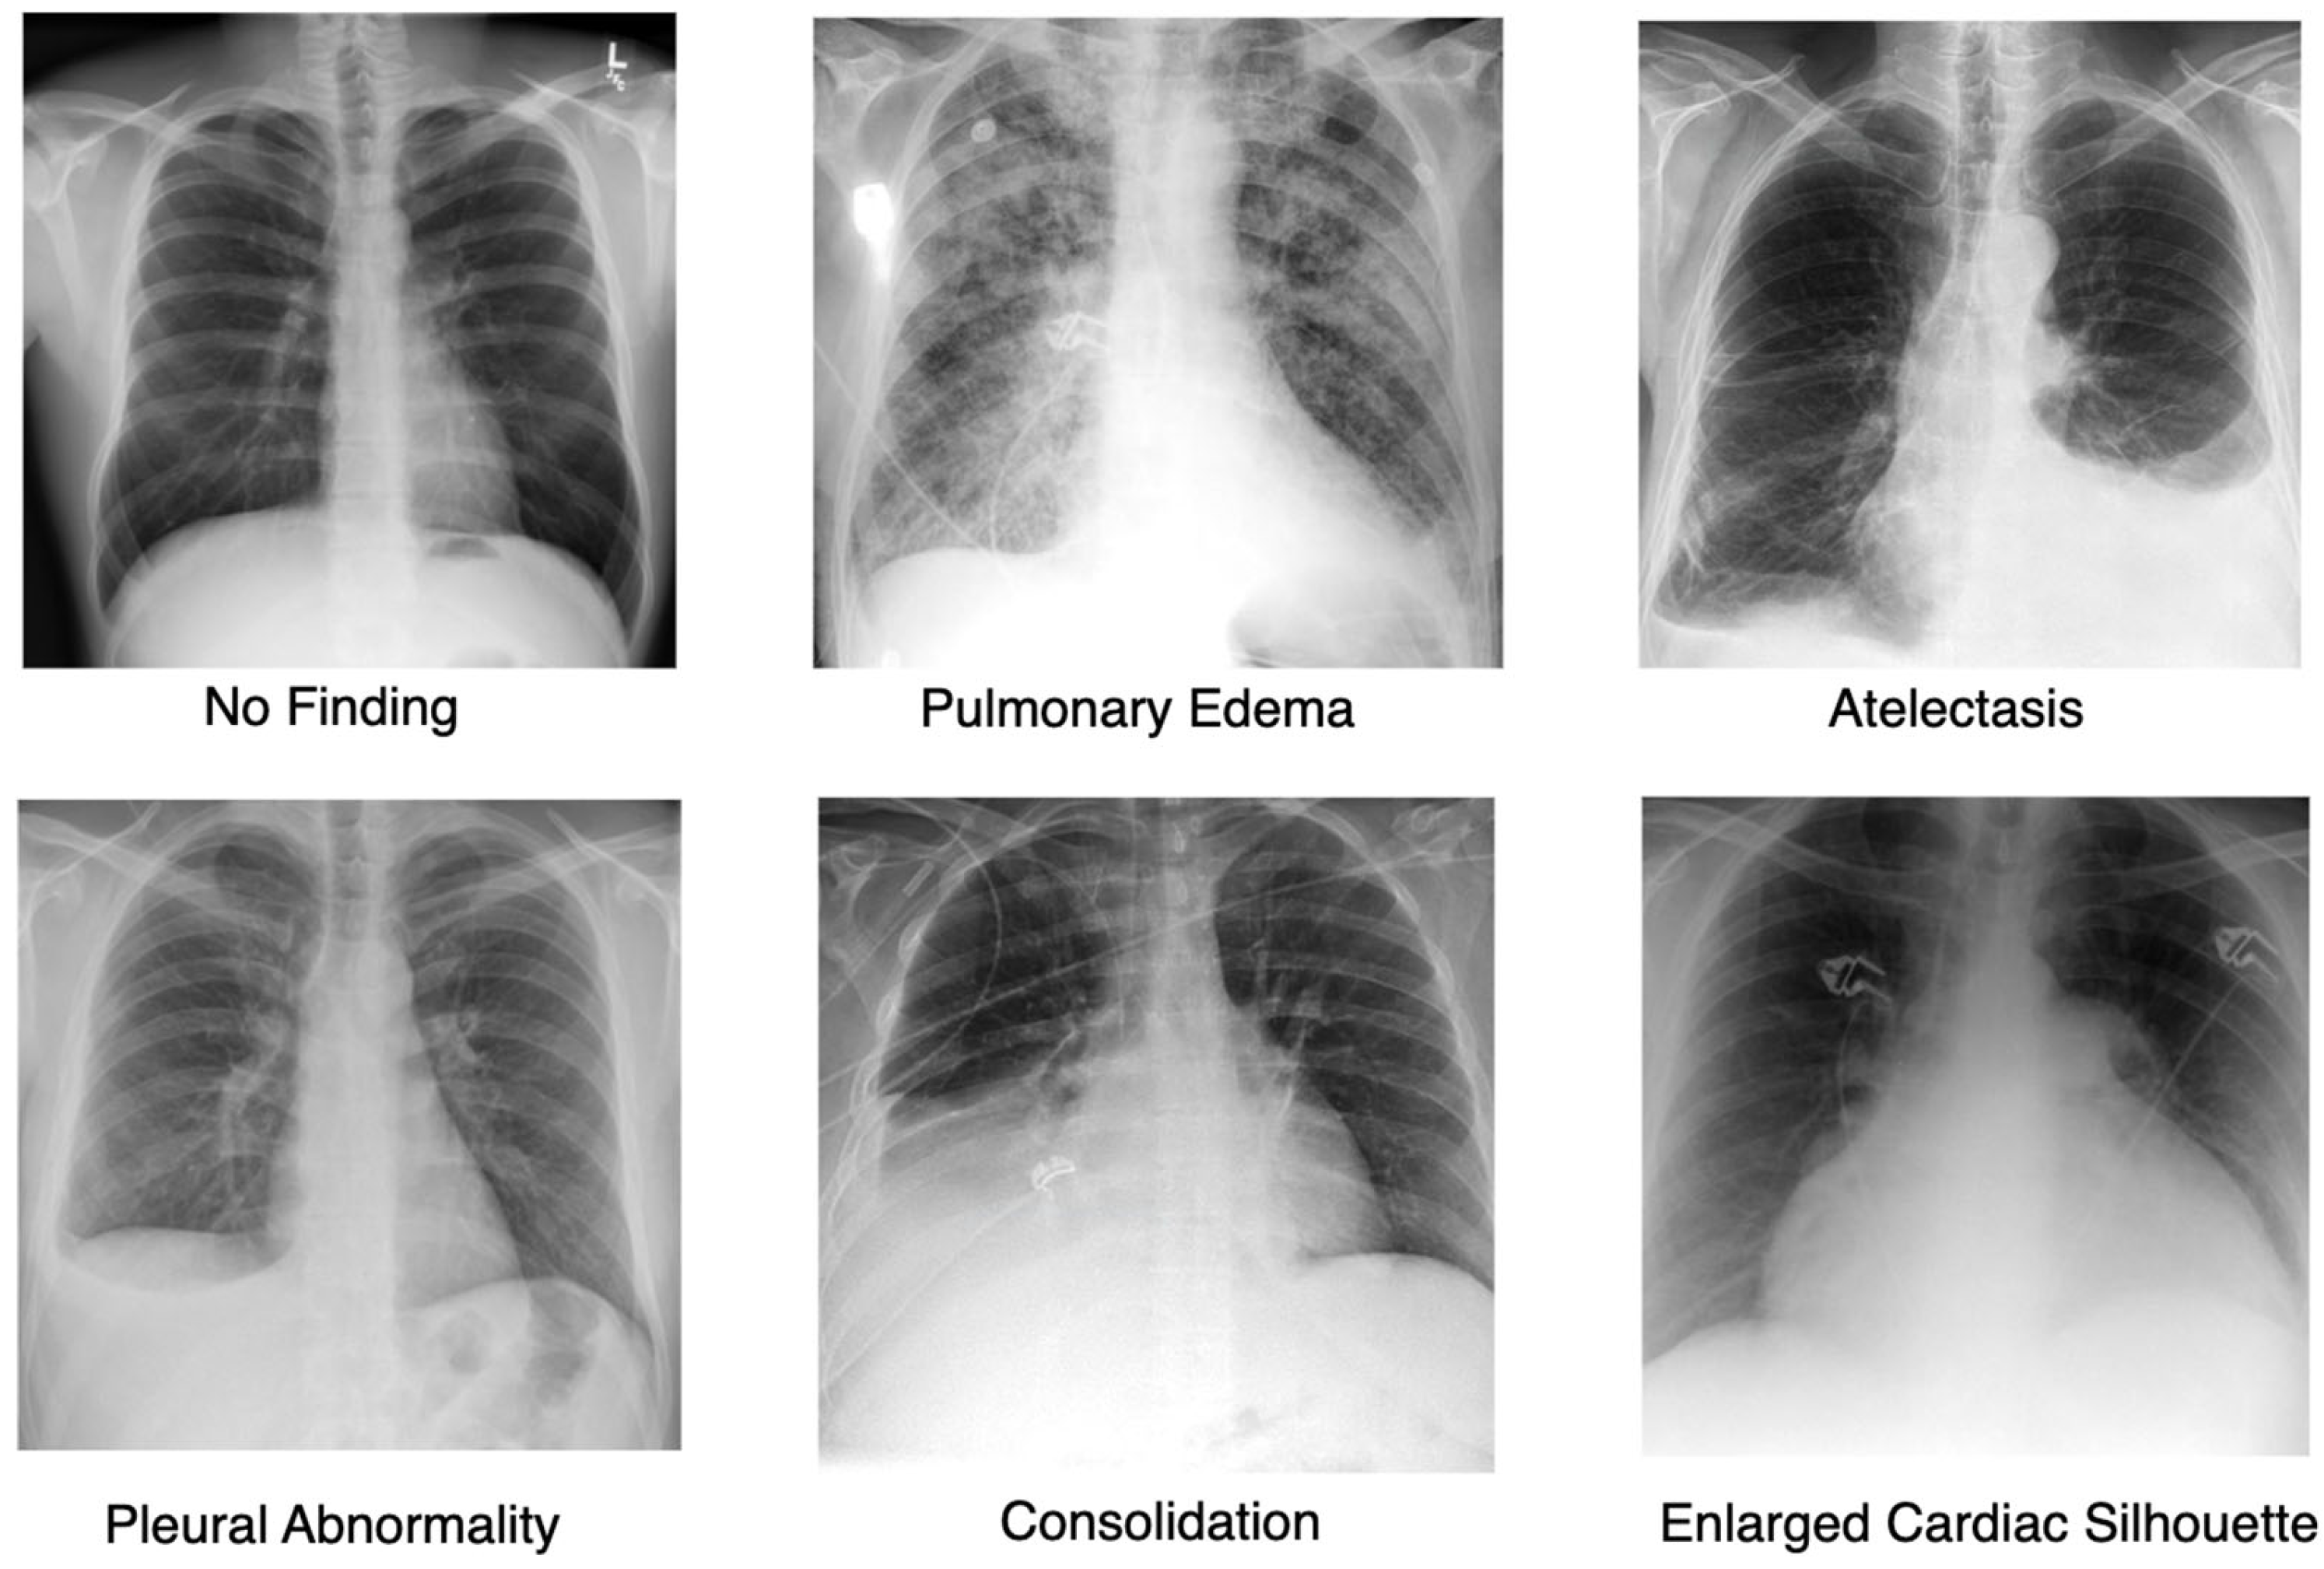

4.1. Dataset

- Bigolin Lanfredi, R.; Zhang, M.; Auffermann, W.F.; Chan, J.; Duong, P.A.T.; Srikumar, V.; Drew, T.; Schroeder, J.D.; Tasdizen, T. REFLACX, a dataset of reports and eye-tracking data for localization of abnormalities in chest x-rays. Sci. Data 2022, 9, 350. [Google Scholar] [CrossRef] [PubMed]

- Johnson, A.E.; Pollard, T.J.; Greenbaum, N.R.; Lungren, M.P.; Deng, C.Y.; Peng, Y.; Lu, Z.; Mark, R.G.; Berkowitz, S.J.; Horng, S. MIMIC-CXR-JPG, a large publicly available database of labeled chest radiographs. arXiv 2019, arXiv:1901.07042. [Google Scholar]